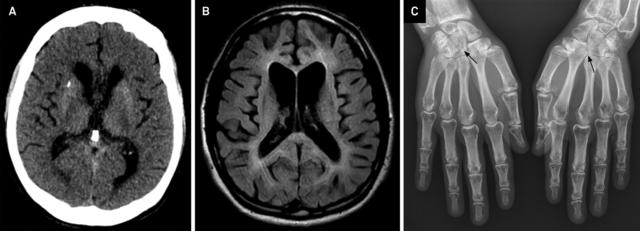

成人 Nasu- 病的影像学特点:

1. 骨骼成像可见多发囊样病灶,导致手腕和脚踝骨折;

2. 头颅 CT 可见基底节区钙化;

3. 头颅 MRI 提示皮质萎缩和非特异性的白质信号改变。

案例 15:46 岁男性,诊断为 Nasu- 病。

图 16 A:头颅 CT 可见豆状核点状钙化;B:FLAIR 提示脑室旁白质轻度高信号,可见皮质萎缩;C:双手平片证实双侧腕骨囊性病灶 [箭]